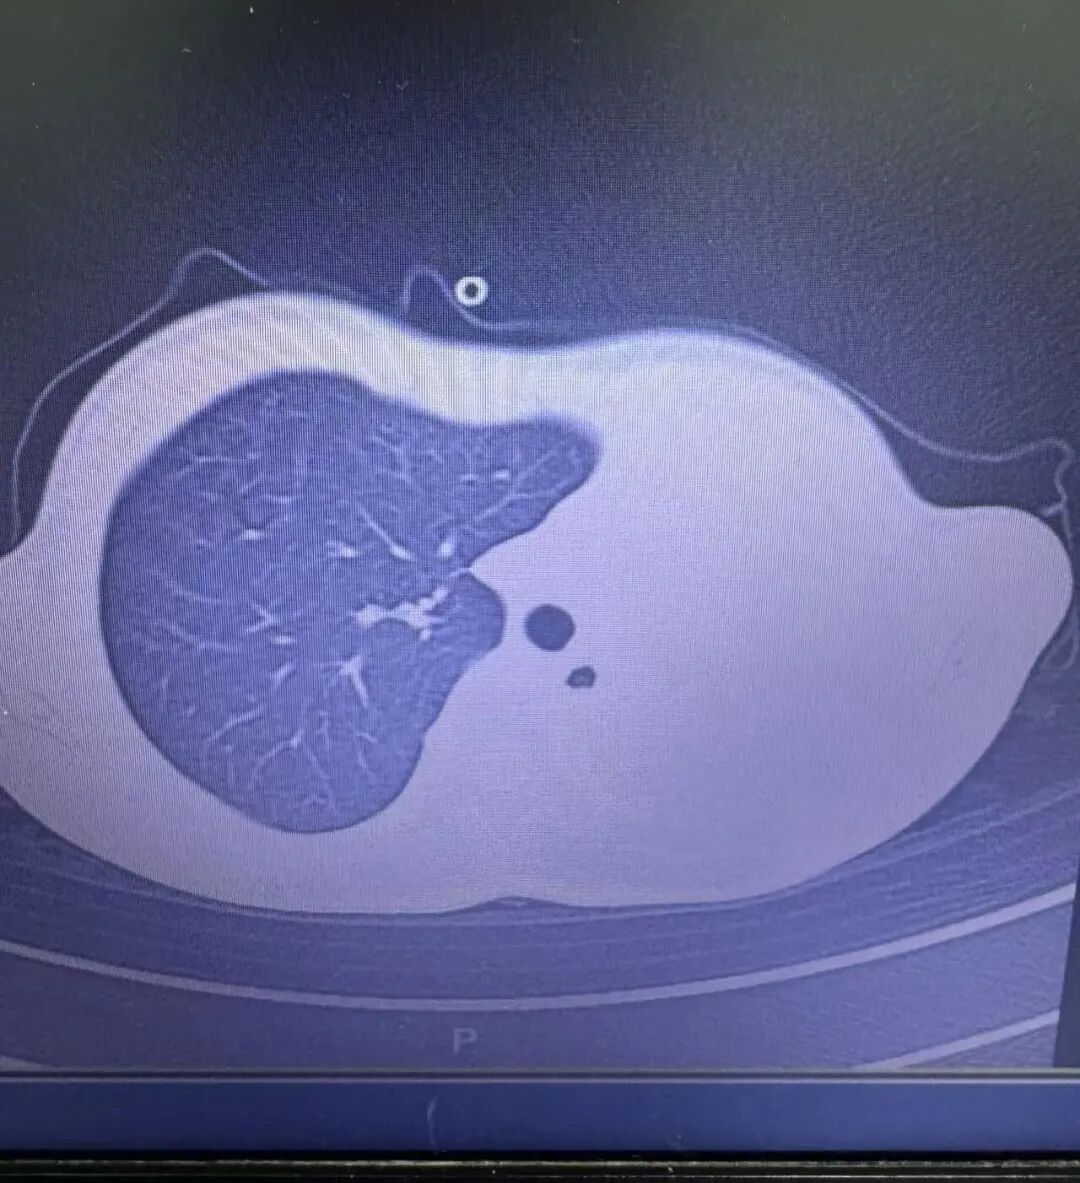

急诊检查结果让医护人员瞬间紧张:验血显示炎症指标大幅上升,胸片更发现左侧肺叶几乎“不工作”了,影像学中变成大片白色,即通常所说的“白肺”,意味着肺功能严重受损,孩子已经缺氧,随时有窒息危险。

图:影像显示肺白了一半

“这是流感合并细菌感染引起的严重肺炎,同时发生了坏死性喉气管支气管炎,一种严重并发症:黏稠痰栓会像树枝一样堵在气道分支处,导致肺部无法正常通气,若不及时处理,几小时就可能威胁生命!”杨子浩主任医师回忆。